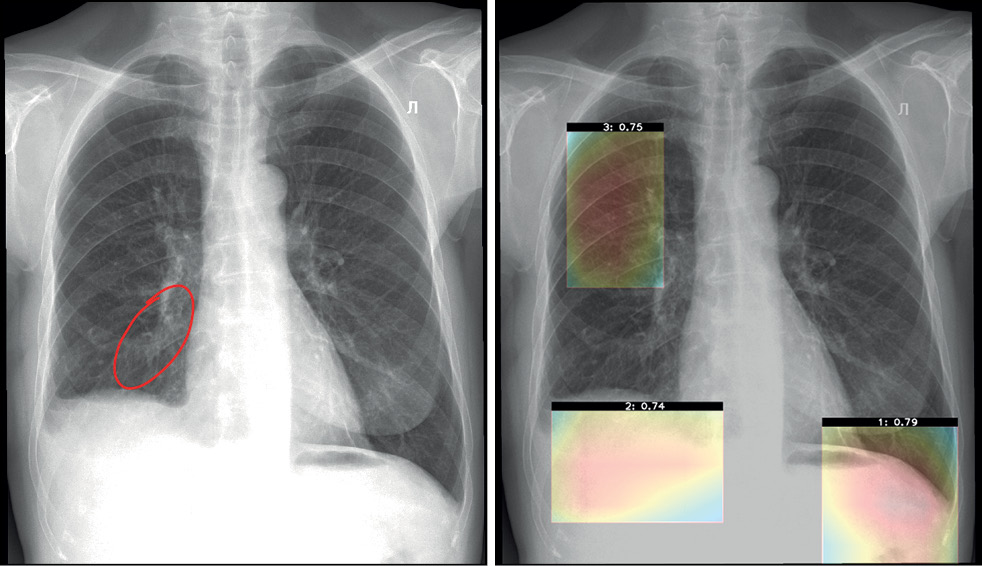

During periodic monitoring, a clinical assessment of software results is also performed by radiologists. Two main evaluation criteria include interpretation (conclusion) and localization (labeling) of an abnormal finding. During the assessment, the response options that clinicians can choose from include full compliance, incorrect assessment, false positive result, and false negative result. For example, the wording “Interpretation: Full compliance” is selected when a specialist fully agrees with the software conclusion, and the wording “Interpretation: Incorrect assessment” is selected when the doctor partially agrees with a software conclusion (e.g., the specialist agrees with the presence of abnormal findings but disagrees with its details, or vice versa, they agree with details but disagree with the general conclusion about the possibility or severity of abnormal findings). If the specialist completely disagrees with the software conclusion, the wordings “Interpretation: False positive result” and “Interpretation: False negative result” are used (Figure 10).

Fig. 10. False negative (the subsegmental atelectasis is not detected in the lower lobe of the right lung): Noncritical noncompliance with basic diagnostic requirements.